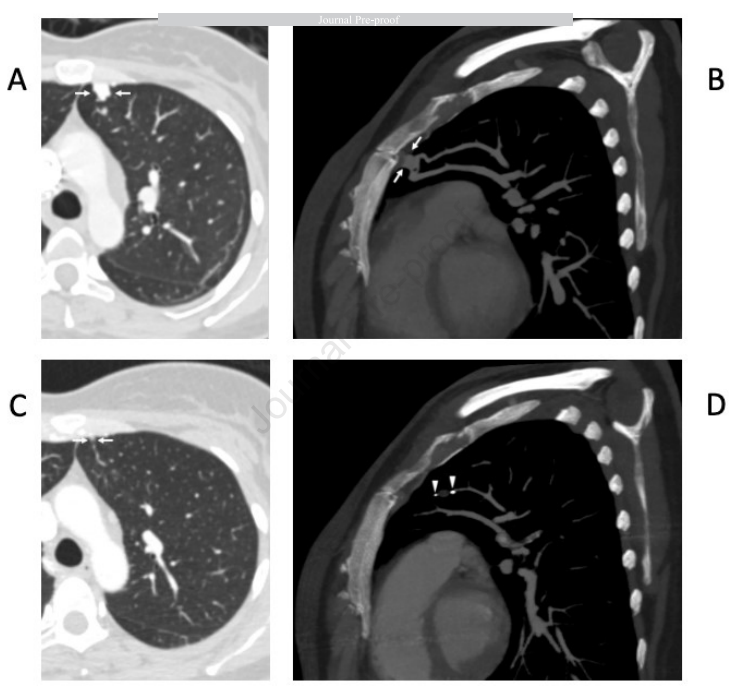

虽然CT是常规治疗后监测的首选方式,但肺血管造影仍然是评估PAVM通畅性的金标准。然而,其临床应用现在主要是治疗性的而非诊断性的。血管造影通常保留用于随访CT有复发证据的病例、CT和TTCE结果不确定的情况,或者患有处于不同治疗和消退阶段的多发PAVMs的患者(图3)。由于其有创性和相对较高的辐射暴露,血管造影不推荐用于常规监测或初始诊断评估。

图3.一名39岁女性HHT患者,患有多发PAVMs。左肺上叶一个供血动脉直径为4mm的PAVM采用MVPS装置进行栓塞治疗。(A)和(B)为栓塞前图像,PAVM以白色箭头标示。(C)和(D)为栓塞后图像,显示囊状结构大小明显消退,无对比剂显影。MVPS装置的末端以白色箭头标示。